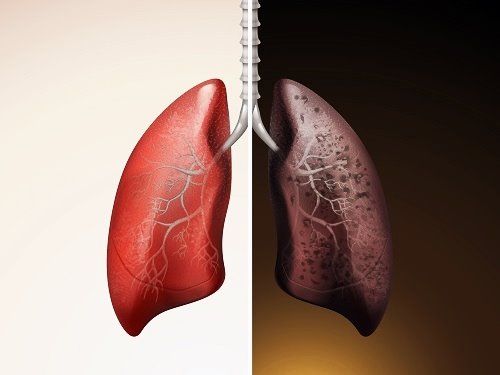

폐암 예방법

흡연은 폐암의 가장 큰 원인 중 하나입니다. 담배를 피우지 않거나 금연하는 것이 폐암 예방에 가장 효과적입니다. 만약 흡연 중이라면 의사나 금연 전문가의 도움을 받아 금연 계획을 수립하는 것이 좋습니다.